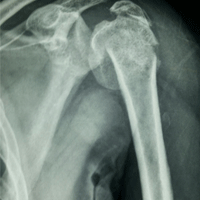

Case:2 Fracture of Neck Humerus with Fracture of Greater Tuberosity

Pre-Op AP

Pre-Op Trausaxillay

Post-Op X-ray